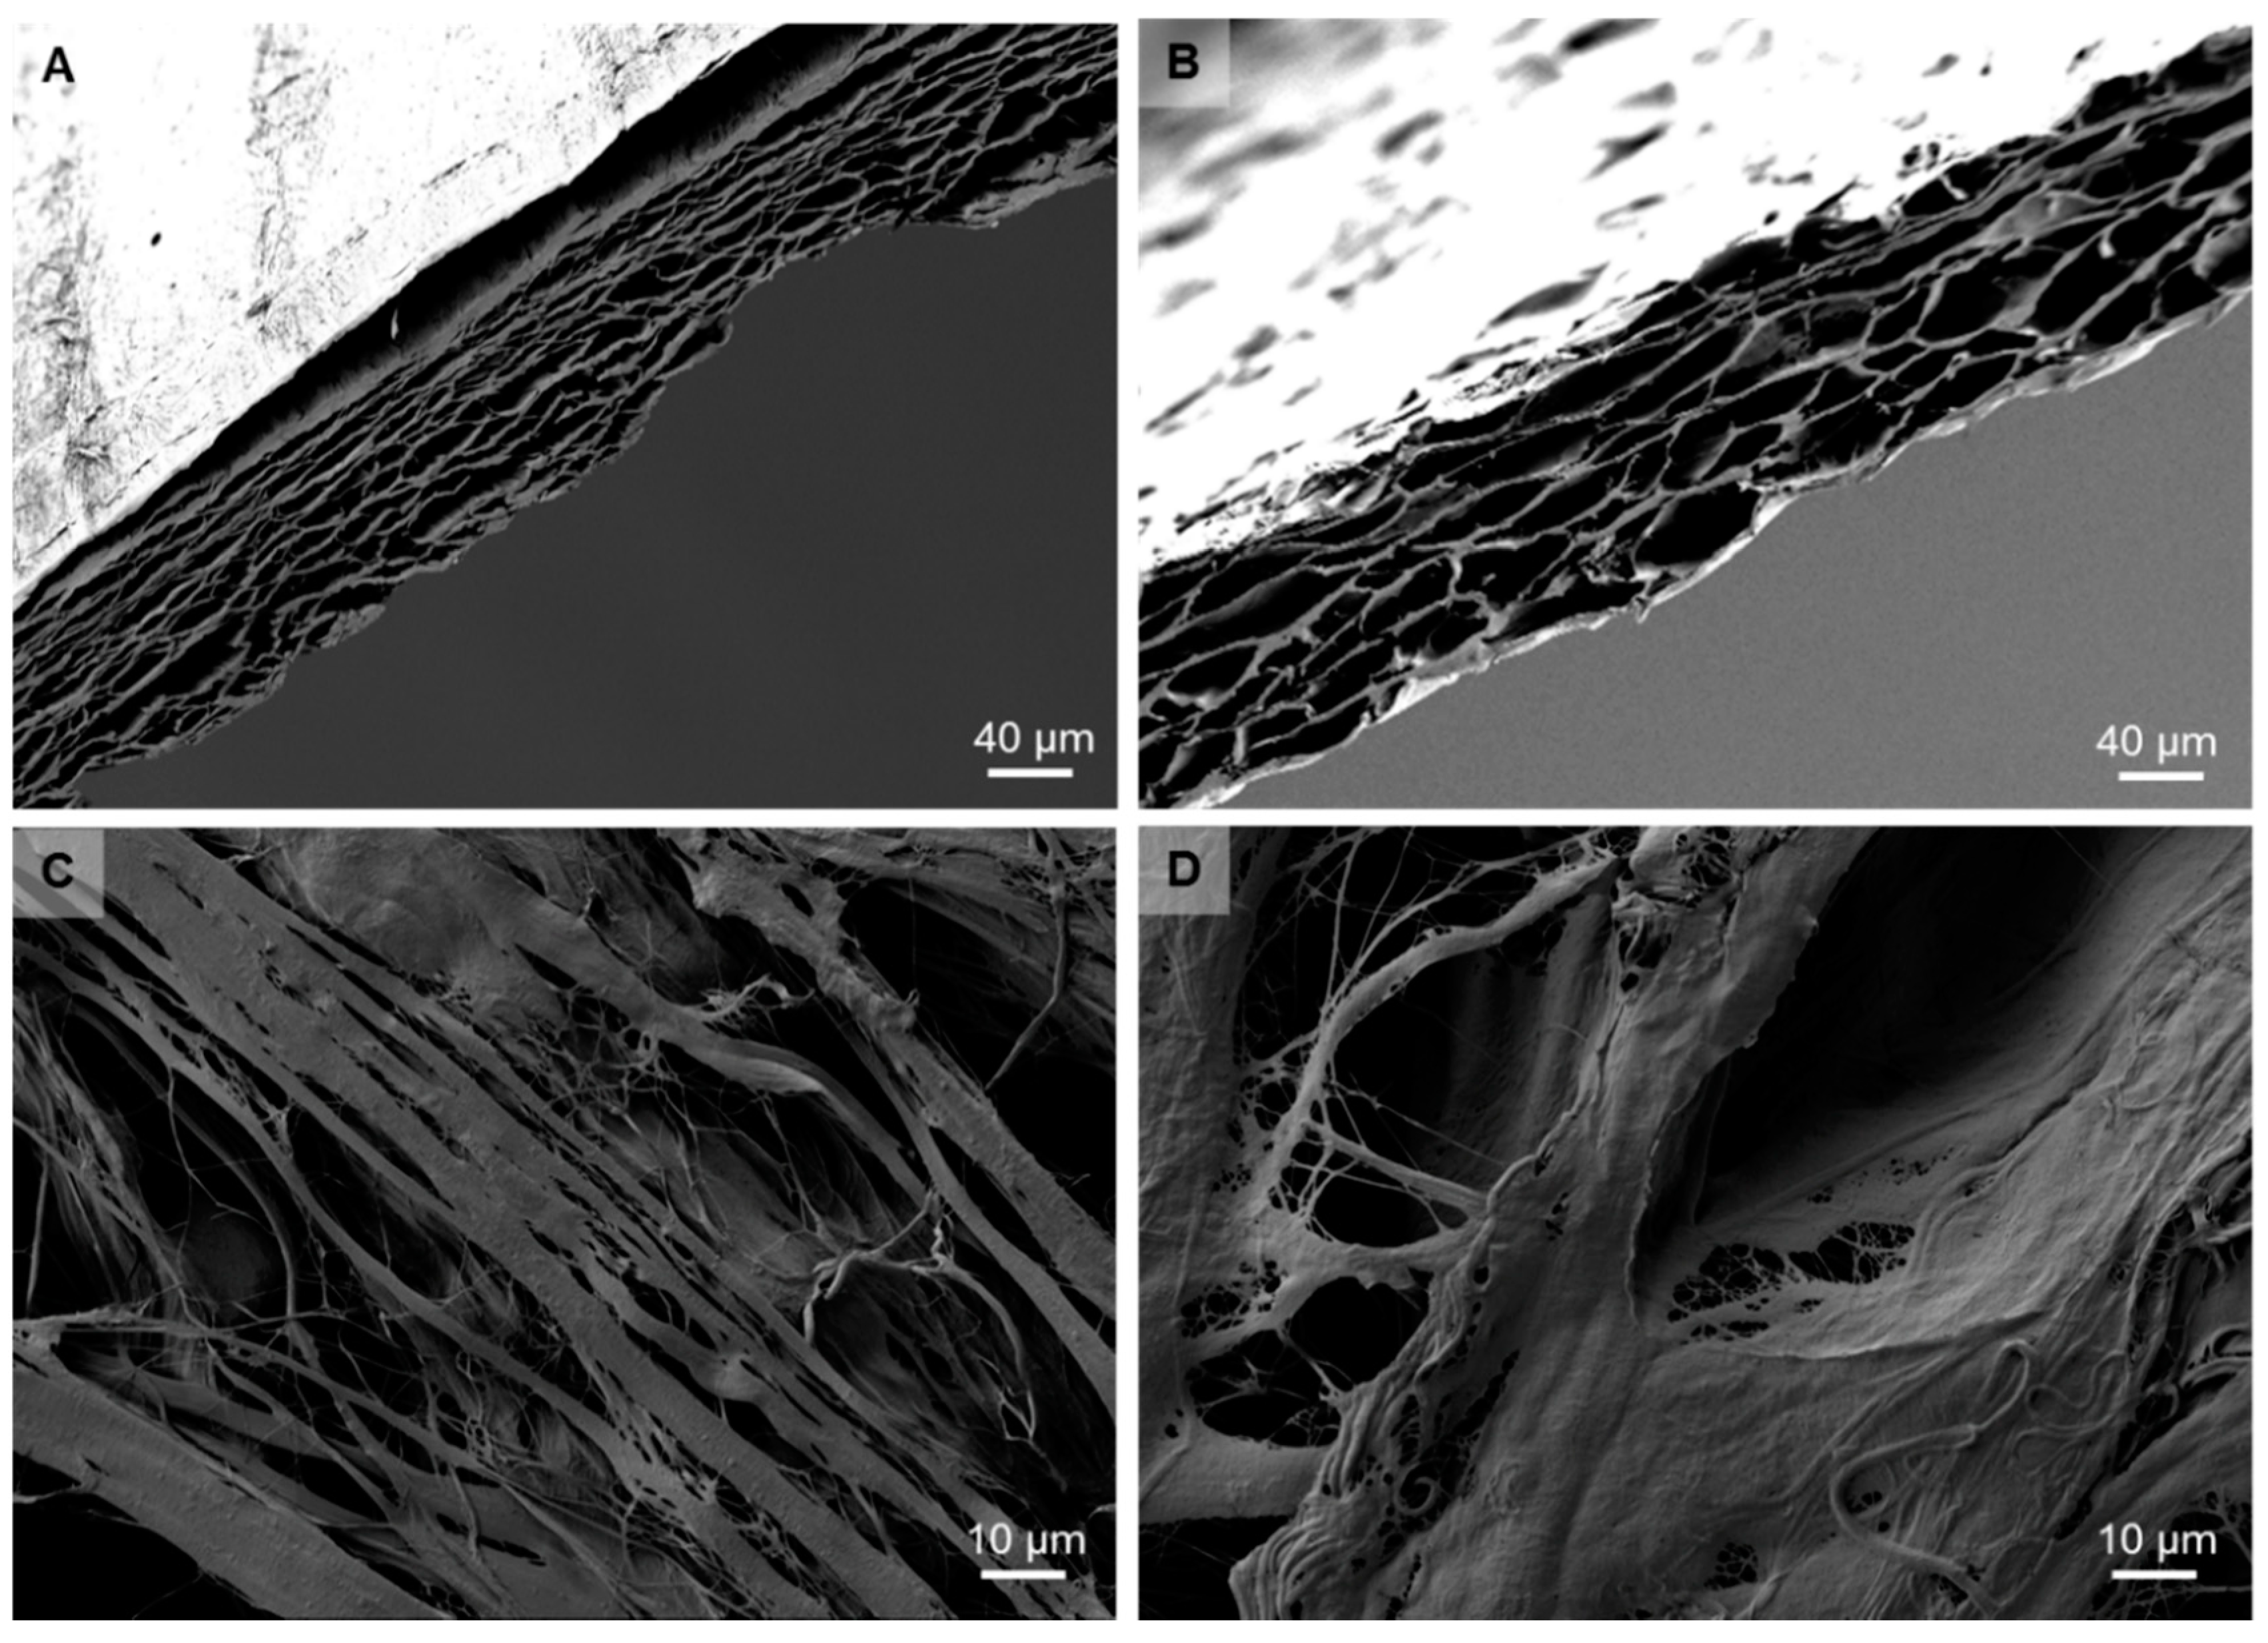

2.1. Structural Analysis of the Membrane